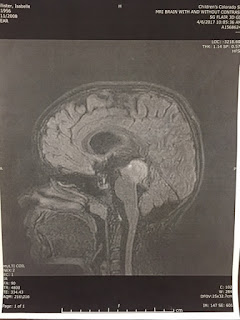

week from Belle’s MRI on Thursday that according to the MRI scan that there is

NO MORE EVIDENCE OF DISEASE!!! Oh my

from our shoulders. MRI below shows the MRI from the diagnosis and then the one recently taken on 4/6/17. The marker of the tumor will always be there, similar to scare tissue.

(MRI above at Diagnosis 12/15/15 )

(MRI above 4/6/17)